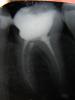

Logos Опубликовано 5 июля, 2008 Автор Поделиться Опубликовано 5 июля, 2008 (изменено) Обработка под цельнолитую коронку ничем не отличается как у цельнолитой металлической, так и у металлокерамической. Другой вопрос, если Ваш доктор ставит Вам штампованную коронку, тогда отличается. Но и тогда золото лучше, чем нержавейка. Ставят литую, не штампованую. Да, кстати, сказали что без напыления, т.к. с напылением хуже - больше взаимодействует с "флорой" рта. Про ЗПС так и не спросил - у нас праздники, день столицы будь она неладна Про вкладку мне ничего не сказали, сделали "пломбу под коронку". Почитал материалы и информацию про вкладки - понимаю, что в моем случае она скорее всего нужна. Спасибо всем за советы. Вчера ходил к другому терапевту по рекомендации, посмотрела - согласилась про коронку. Пломба уже стоит, стоит аккуратно, не высверливать же ее (зачем лишний раз остаток зуба травмировать), чтобы вкладку ставить. Сделал рентген: Изменено 5 июля, 2008 пользователем Logos Ссылка на комментарий

zybnaya feya Опубликовано 5 июля, 2008 Поделиться Опубликовано 5 июля, 2008 Ставят литую, не штампованую. Да, кстати, сказали что без напыления, т.к. с напылением хуже - больше взаимодействует с "флорой" рта. Про ЗПС так и не спросил - у нас праздники, день столицы будь она неладна Про вкладку мне ничего не сказали, сделали "пломбу под коронку". Почитал материалы и информацию про вкладки - понимаю, что в моем случае она скорее всего нужна. Спасибо всем за советы. Вчера ходил к другому терапевту по рекомендации, посмотрела - согласилась про коронку. Пломба уже стоит, стоит аккуратно, не высверливать же ее (зачем лишний раз остаток зуба травмировать), чтобы вкладку ставить. Сделал рентген: Вам сначала надо каналы нормально перелечить,т.к. запломбированы они одной пастой-чревато рассасыванием. А потом уже и вкладочку зафиксировать Ссылка на комментарий

Doc Опубликовано 5 июля, 2008 Поделиться Опубликовано 5 июля, 2008 Вчера ходил к другому терапевту по рекомендации, посмотрела - согласилась про коронку. Пломба уже стоит, стоит аккуратно, не высверливать же ее (зачем лишний раз остаток зуба травмировать), чтобы вкладку ставить. Если Вам нужно поменьше возиться, то ставьте на эту пломбу коронку и ждите пока неприятности не вылезут. В таком варианте они должны повылазить довольно скоро, от полугода-года, до лет пяти. Если ОЧЕНЬ повезет, то немного дольше проходите. Если хотите на бОльший срок и без неприятностей, то нужно не только пломбу вынимать, но и каналы перелечивать, пломбировать гутапперчей, потом ставить вкладку, потом коронку. При подобной степени разрушения зуба вкладка показана на 100%. Ссылка на комментарий